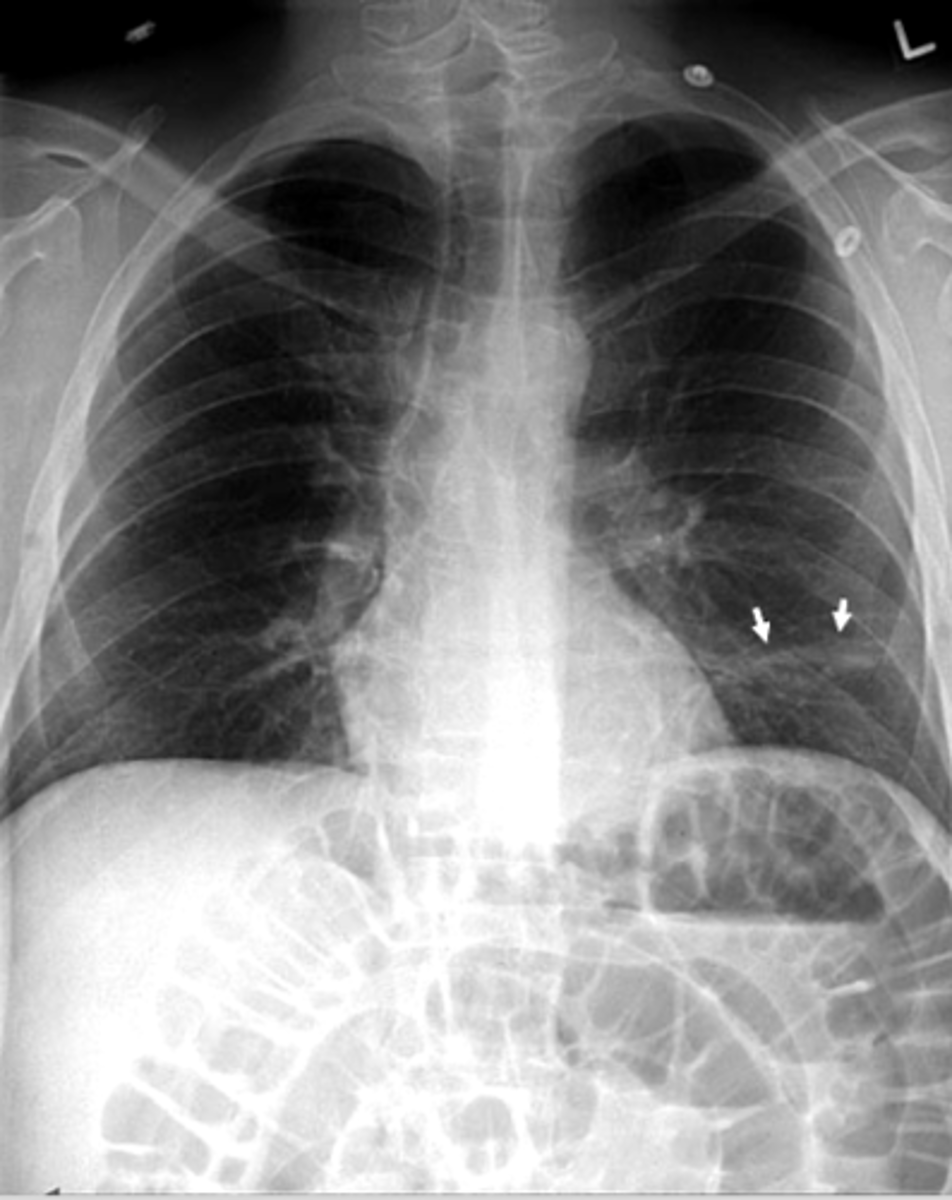

Bronchiectasis

-tram lines

Dx. What is this finding?

<p>Dx. What is this finding?</p>

Often associated with COPD or emphysema but bullae can be present in normal asymptomatic patients. (this pt has emphysema)

What dz are blebs and bullae associated with?

<p>What dz are blebs and bullae associated with?</p>

-Flattening of hemidiaphragms with blunting of costophrenic angles.

-Increased AP diameter of chest on lateral view (barrel chest)

-Presence of bullae or large air cavities

What x-ray findings are found in advanced stages of COPD/emphysema?